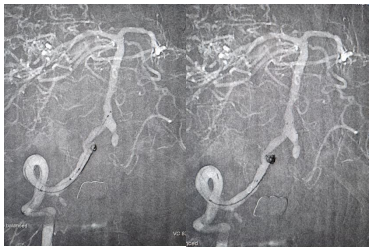

患者高先生,70岁,患有高血压病多年。2年前曾行冠状动脉搭桥术,平素规律服药。2个月前,他因左上肢突然麻木被送至清华大学垂杨柳医院急诊科就诊。头颅CT提示右侧顶叶少量蛛网膜下腔出血。后入住神经外科进一步诊治,全脑血管造影(DSA)结果显示:右侧椎动脉起始部重度狭窄约70%,左侧椎动脉颅内段闭塞;右侧椎动脉颅内段存在直径约3.5×2毫米的夹层动脉瘤;右侧颈内动脉颅外段存在重度狭窄,左侧颈内动脉通过前交通动脉代偿。

▲右侧椎动脉起始重度狭窄左侧椎动脉颅内段闭塞

▲右侧椎动脉V4段夹层动脉瘤